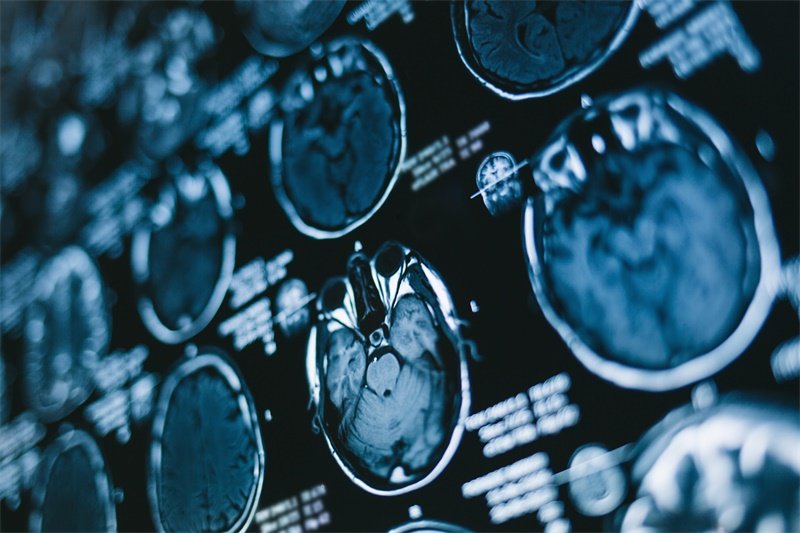

颅内海绵状血管瘤是脑血管畸形的一种类型,由众多薄壁血管组成,呈海绵状。当瘤体体积较大时,会对周围的脑组织、神经和血管等结构产生明显影响,引发一系列复杂的症状。了解这些症状,对于疾病的早期发现、诊断和治疗具有重要意义。接下来,我们将详细介绍颅内大的海绵状血管瘤常见的7种症状。

颅内大的海绵状血管瘤可引发多种复杂症状,这些症状严重影响患者的身体健康和生活质量。头痛、癫痫发作、神经功能障碍、视力障碍、听力障碍、语言功能障碍以及颅内出血相关症状,每一种症状都对患者的身体和心理造成了不同程度的困扰。了解这些症状,有助于早期发现颅内大的海绵状血管瘤,及时采取有效的治疗措施,降低疾病的危害。早期诊断和治疗对于改善患者的预后、提高生活质量至关重要。